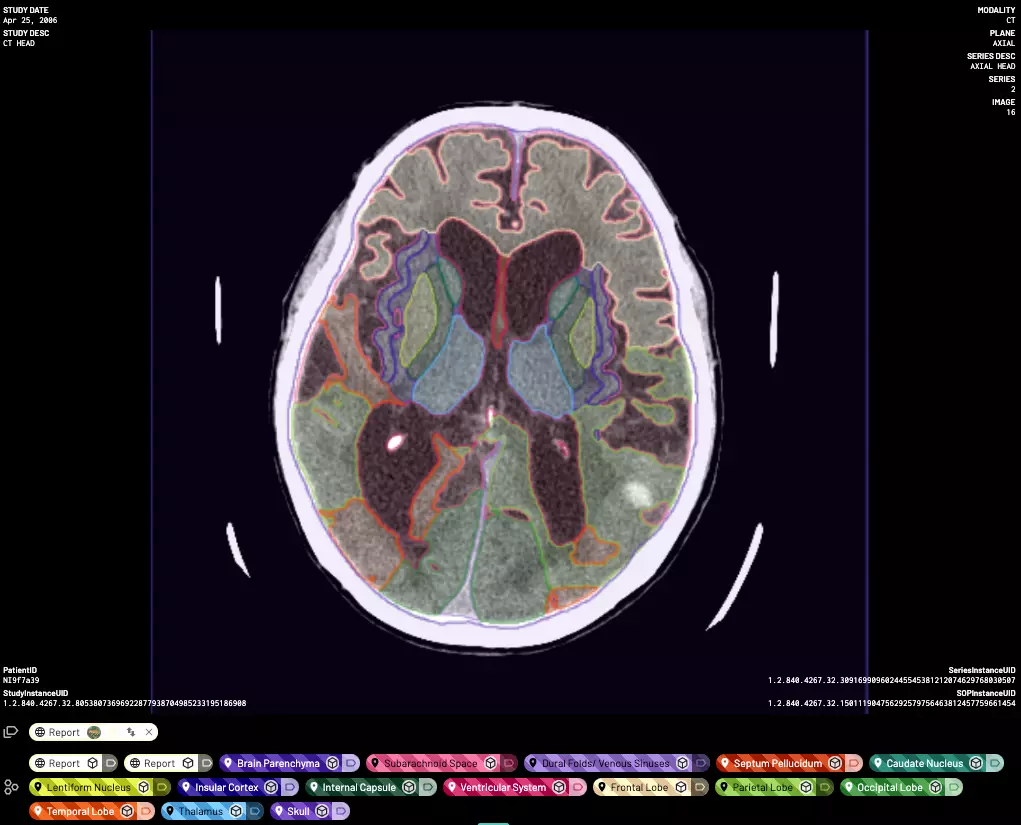

Encord has a clear niche: it focuses heavily on medical imaging. Also, it is built for end-to-end data operations across annotation, curation, and evaluation. Encord supports multi-modal annotations: DICOM & NIfTI can be labeled alongside text, audio, and video.

Its medical viewer is strong, and the platform supports 2D, 3D, and multi-slice annotation with axial, sagittal, and coronal planes. You get tools for segmentation, polygons, and contours with active learning.

Encord DICOM Annotation

Its audit logs, SSO, and roles support enterprise governance necessary for medical image labeling. Its privacy and compliance features help hospital teams work with sensitive data easily. Radiologists can label scans inside a structured review workflow.

Why use it:

- Strong medical imaging support

- High-quality segmentation tools

- Active learning for medical annotation

- HIPAA-aligned workflows

Pricing: Pay-as-you-go. Your invoice depends on your project, quotes, and team members. To label DICOM & NIfTI files, you need at least a Starter pack.

Best for: Hospitals and medical research labs that need reliability.